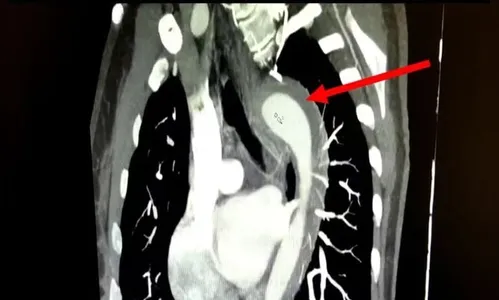

Durante o orgasmo, a paciente relatou uma dor torácica súbita e intensa, que se irradiava para as costas, acompanhada de falta de ar e náuseas. Ao procurar atendimento médico, os exames identificaram um hematoma intramural, uma forma de hemorragia na parede da aorta, caracterizando um quadro de Síndrome Aórtica Aguda (SAA).

Essa condição é considerada uma emergência médica. Sem tratamento, a taxa de mortalidade da SAA aumenta em cerca de 1% a cada hora. Felizmente, a paciente foi submetida a uma cirurgia de emergência e teve uma boa recuperação, recebendo alta apenas três dias após o procedimento.